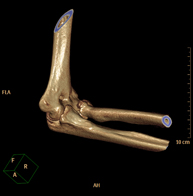

Exploració radiològica que mitjançant un sistema de raigs X i detectors que giren al voltant del pacient i que reconstrueixen les imatges per ordinador (TC Multidetector), permet l'estudi detallat dels ossos, els músculs i les articulacions de l'espatlla. - TC de colze

Exploració radiològica que mitjançant un sistema de raigs X i detectors que giren al voltant del pacient i que reconstrueixen les imatges per ordinador (TC Multidetector), permet l'estudi detallat dels ossos, els músculs i les articulacions del colze. - TC de la mà